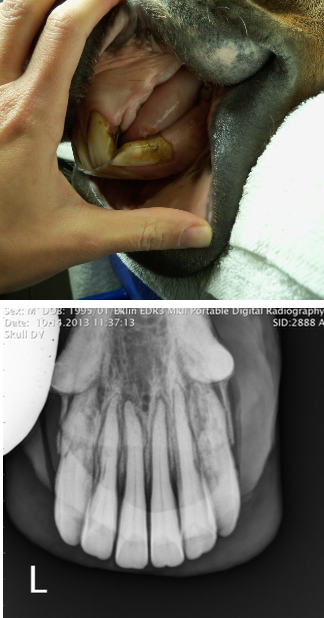

what is EOTRH?

progressive dental condition involving the incisors, canines, and premolars of aged horses internal and external resorption of dental structures and production of irregular cementum

what lesions/changes are seen with EOTRH?

gingival recession, calculus deposition, and firm bulbous enlargement of incisive bone over incisive reserve crowns

what is the treatment for EOTRH?

extraction of incisors